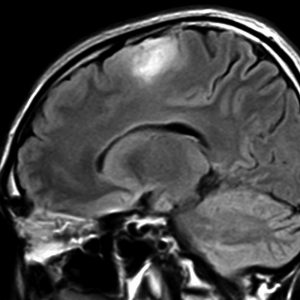

diffuse, infiltrative びまん性のもの

染み込むように左前頭側頭葉から島回に広がるAAです。T2/フレア像でにじむように広がり,ガドリニウム増強されません。グレード 2 (びまん性星細胞腫)と区別が難しいものです。

もちろん手術摘出できないもので,生検手術のみを行います。この大きさのものに60グレイの放射線治療をすれば高度の認知機能低下は避けられませんから,患者さんと照射線量をよくよく相談します。でもAAは放射線化学療法で長期生存が望めます。50-54グレイの線量が選択されます。